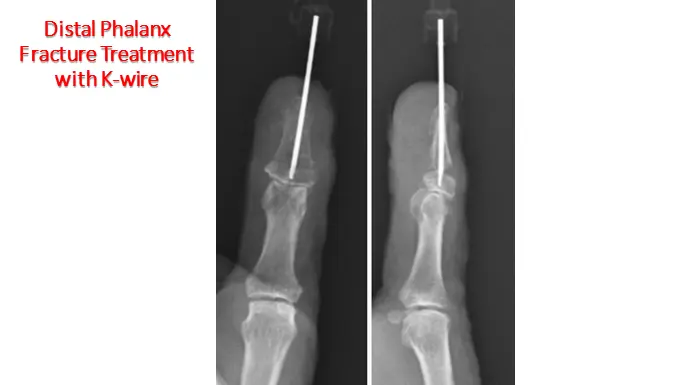

2. Surgical Treatment (Less Common)

Surgery is considered when:

- The fracture is severely displaced

- There is joint involvement

- Open fractures with significant soft tissue injury

- Tendon injuries (e.g., mallet finger)

Procedures may include:

- K-wire fixation (small pins to stabilize bone)

- Nail bed repair

- Debridement for contaminated wounds